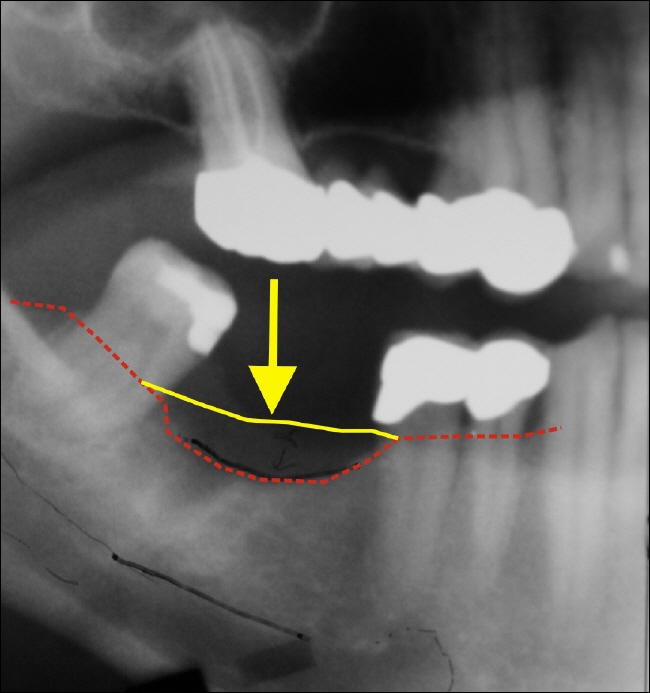

Eine unversorgte Lücke Das Bild oben zeigt eine Zahnlücke im Unterkiefer (gelber Pfeil). Das langjährige fehlen des Zahnes blieb in diesem Fall nicht ohne Folgen. Der Knochen ist in seiner Höhe stark abgebaut. Zum Vergleich, die gelbe Linie entspricht dem ehemaligen Knochenverlauf, die rote gestrichelte Linie zeigt den momentanen Knochenverlauf. Das was zwischen den Lienien ist, ist die verlorene Knochenhöhe. In diesem Fall sind das etwa 7 mm bisher.